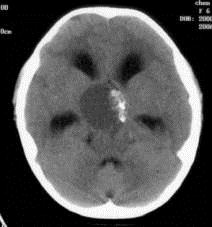

病历摘要:??患者女性,6岁,半年来感觉视力模糊,近10天出现反复头痛,间有恶心呕吐,精神转差,查体:神志清楚,身高90cm,体重25Kg,血压90/55...

问题 病历摘要:??患者女性,6岁,半年来感觉视力模糊,近10天出现反复头痛,间有恶心呕吐,精神转差,查体:神志清楚,身高90cm,体重25Kg,血压90/55mmHg,右眼视力4.6,左眼视力4.8,双侧视乳头水肿,颈软,伸舌居中,四肢肌张力正常,肌力5级,双侧Babinski征(-)。 患者术后第三天,神志逐渐转差,浅昏迷状态,并出现癫痫大发作,体查:颈抵抗,HR110次/分,T38.5℃,BP90/52mmHg,中心静脉压10mmHO,右侧瞳孔2.5mm,光反射迟钝,左侧瞳孔2.0mm,光反射灵敏,刺痛右侧肢体可以定位,左侧肢体见轻微肌肉收缩动作,右侧Babinski征(-),左侧Babinski征(+)。考虑患者病情加重的最可能原因有?

选项 A.高渗性昏迷 B.低渗性昏迷 C.水中毒 D.感染性休克 E.缺血缺氧性脑病 F.脑血管痉挛 G.脑梗塞 H.脑出血 I.无菌性脑膜炎

答案 GH